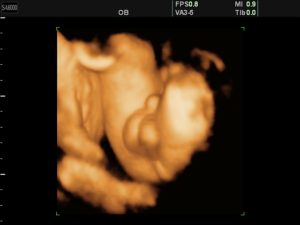

Как вы уже поняли, ошибок при УЗИ не так много, и каждой из них есть конкретное объяснение. Стоит отметить, что минимальный процент ошибок показывает трёхмерная диагностика.

На 3D оборудовании специалист может увидеть гораздо больше: в данном случае ультразвук в его руках превращается в поистине уникальный инструмент, который во много раз превосходит оборудование для двухмерной диагностики. Внешне аппараты УЗИ, как трёхмерные, так и двухмерные, выглядят одинаково.

Датчик в 3D диагностике в несколько раз превышает по размерам стандартный, так как внутри у него расположен двухмерный датчик, который постоянно перемещается и передает на экран монитора объемное изображение. То есть, трёхмерное УЗИ не появилось бы, не будь двухмерного. Да и сейчас без двухмерного датчика оно не может существовать.

Наиболее эффективным считается оборудование, имеющее возможность получения снимка в трехмерной проекции, поскольку диагностика малыша получается одновременно в 3 плоскостях.Трехмерное УЗИ позволяет получить более точную информацию